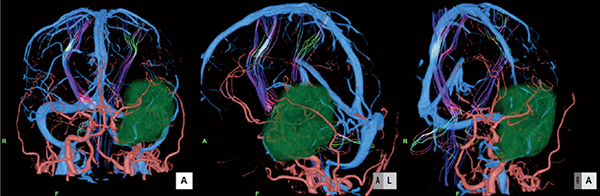

さらに、手術時の開頭野を想定し、頭蓋骨を取り除き脳表のみ切り込んでいくことで、脳表から腫瘍までの距離、腫瘍の栄養血管や錐体路の位置関係の把握ができ、術前のシミュレーションに役立つ(図4)。

図4 術前シミュレーション画像